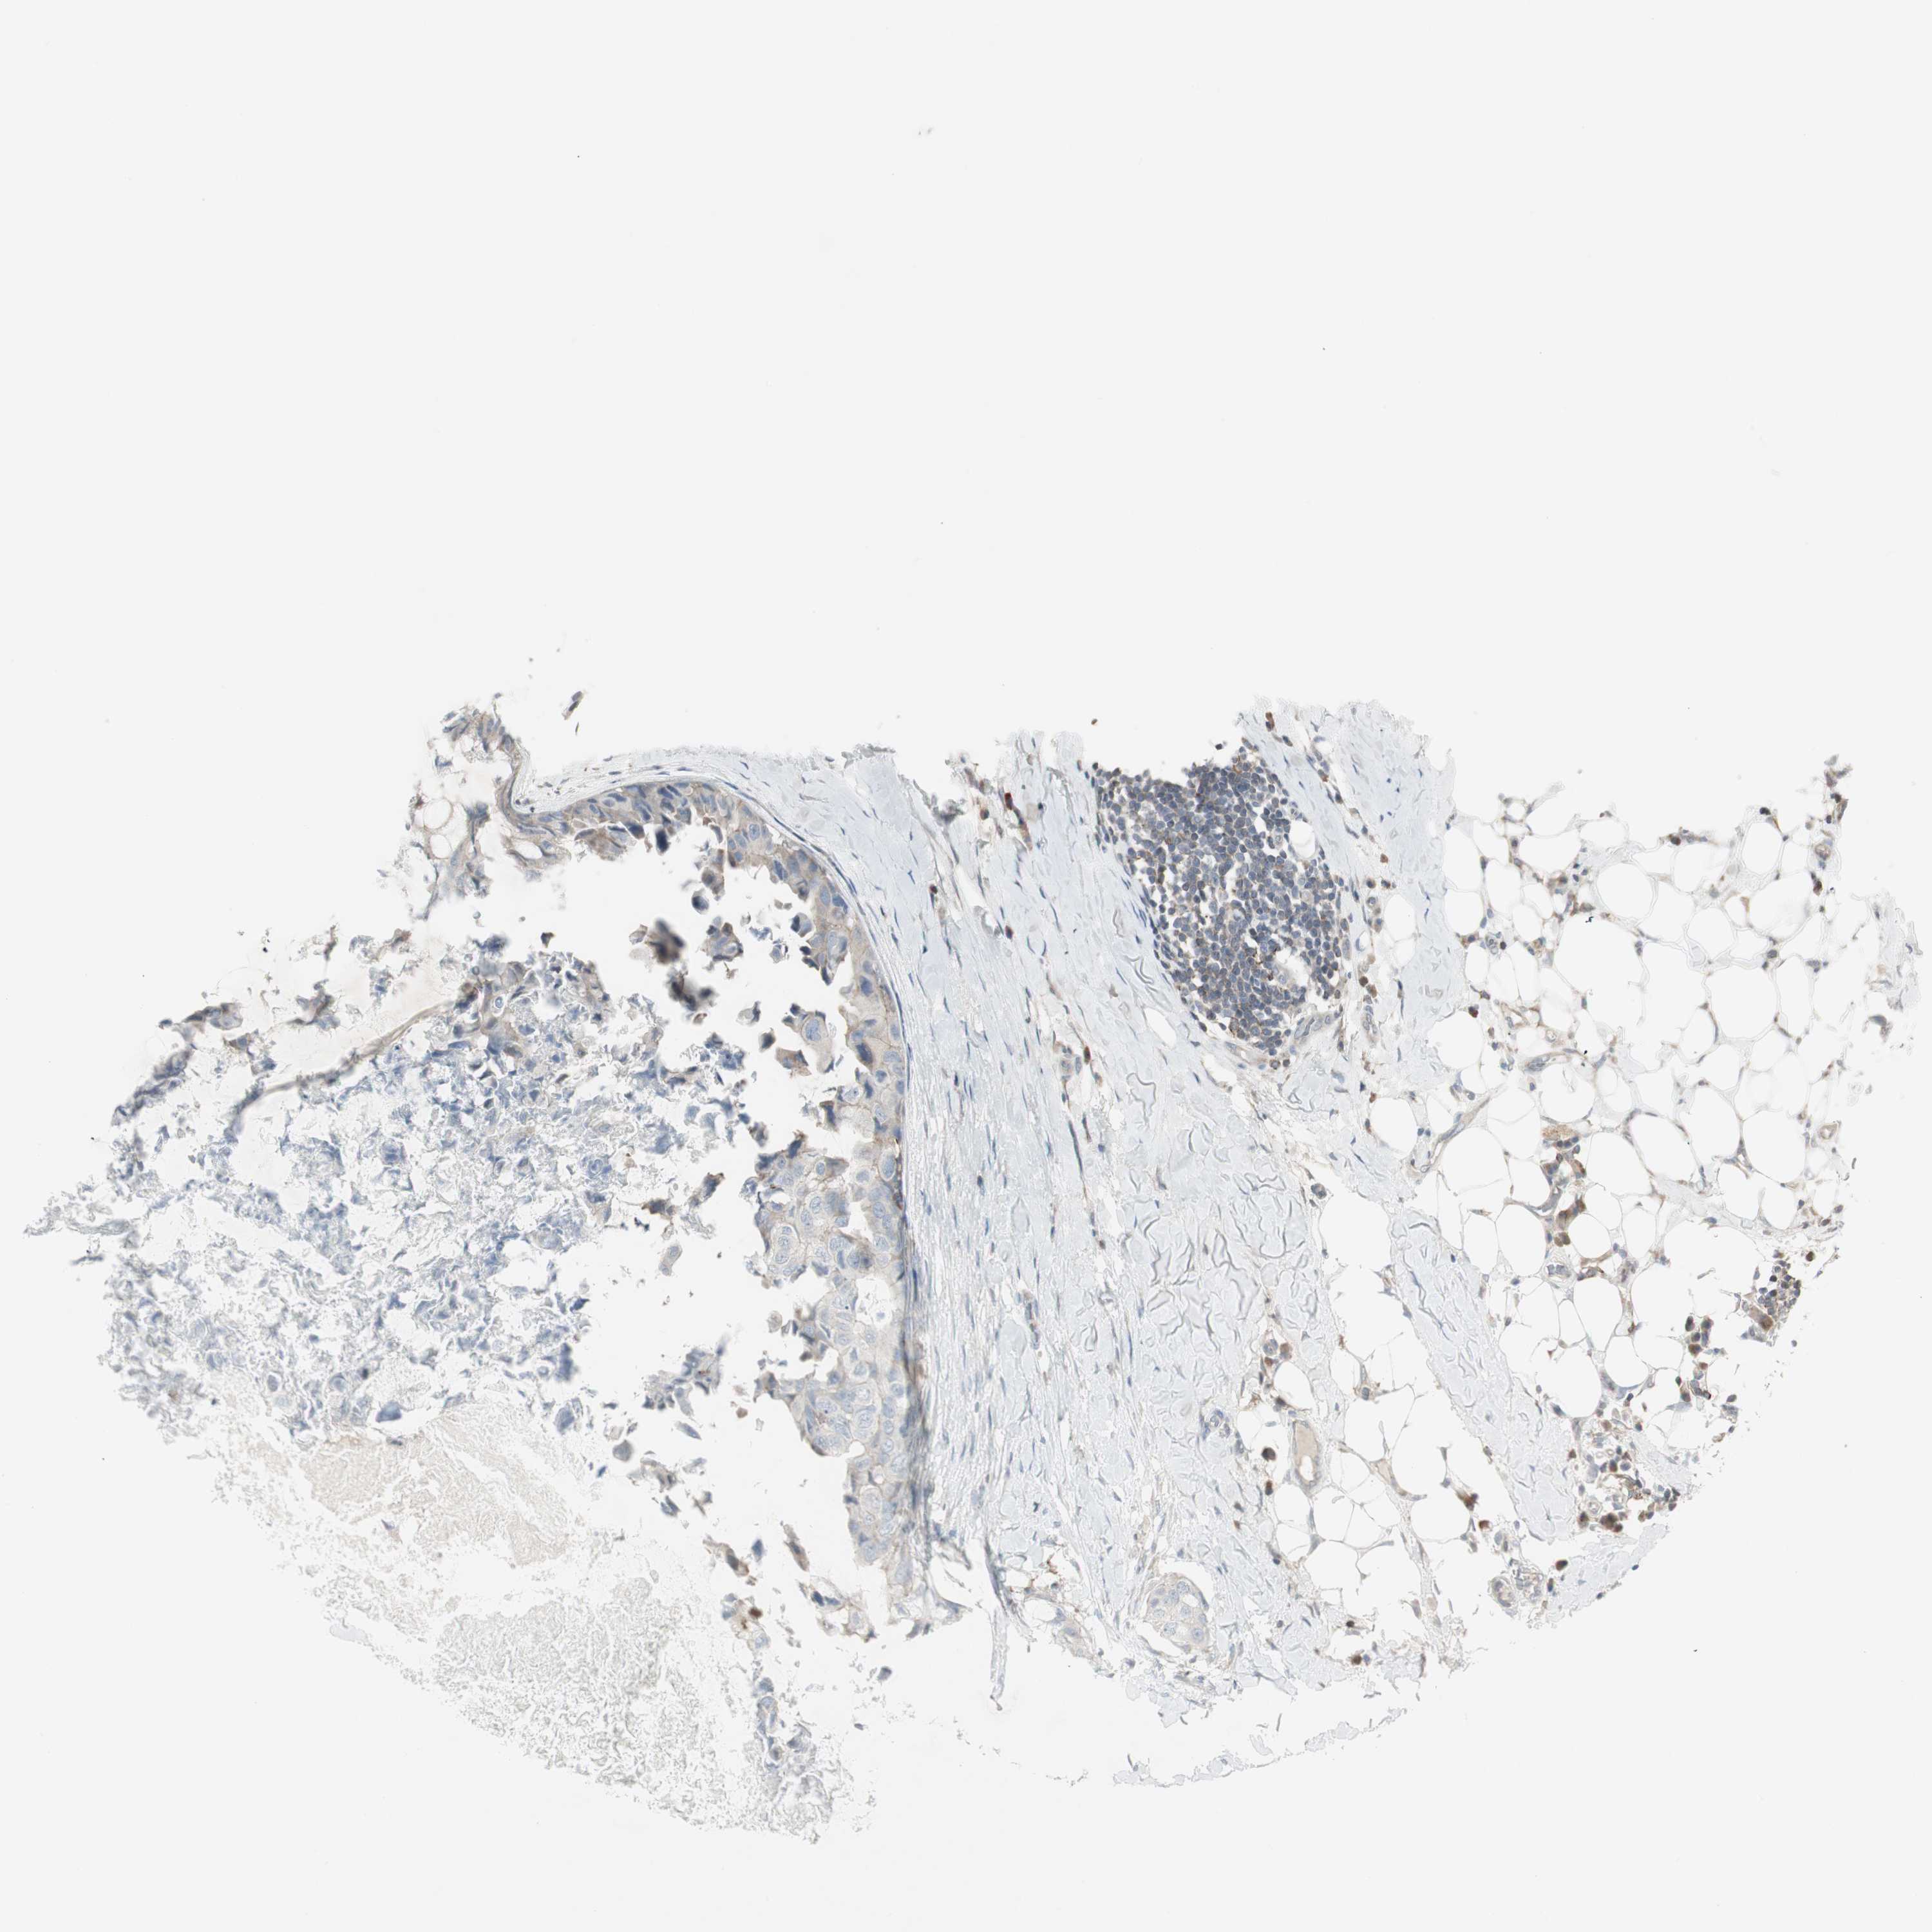

CANCER BREAST CANCER Show tissue menu

BRCA TCGA BRCA VALIDATION PROTEIN EXPRESSION